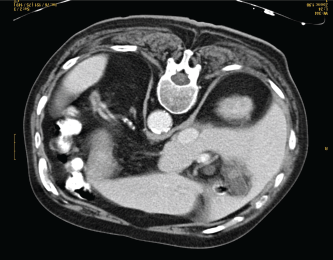

Five cycles of chemotherapy with cyclophosphamide, doxorubicin, vincristine, prednisone, and rituximab (R-CHOP) and one cycle with cyclophosphamide, vincristine, prednisone, and rituximab (R-CVP) were administered reaching complete response (Figure 2).

Figure 2. CT-scan at the end of chemotherapy treatment showing complete response.